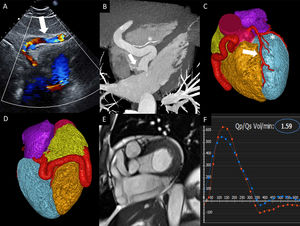

- Evaluación multimodal de un aneurisma de arteria coronaria con fístula arteriovenosa

- Marcos Ferrández-Escarabajal, Solomon W. Bienstock, Gina LaRocca

- Rev Esp Cardiol. 2024;77:973